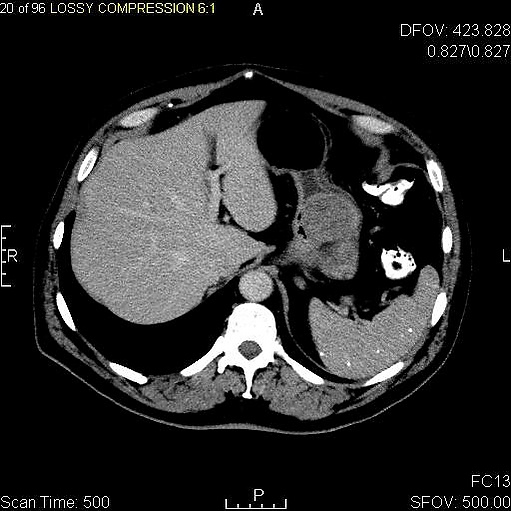

Крупные ГИСО

По мере роста опухоли, она может проецироваться снаружи от органа (экзофитный рост) и/или в просвете органа (интралюминальный рост); чаще всего ГИСО растут экзофитно, таким образом большая часть опухоли располагается в проекции брюшной полости. Если увеличение объёма опухоли опережает рост её кровоснабжения, опухоль может некротизироваться в толще, с формированием центральной зоны жидкостной плотности и кавитацией, что может приводить к изъязвлению и формированию соустья с полостью органа. В этом случае исследование с бариевой взвесью может демонстрировать газ, уровни газ/жидкость или депонирование контрастного препарата в этих областях.[17][18] При КТ с контрастным усилением крупные ГИСО выглядят негомогенно, в связи с неоднородностью структуры опухоли, обусловленной участками некроза, кровоизлияниями и полостями, что радиологически проявляется контрастированием опухоли преимущественно по периферии.[16]

Злокачественность может проявляться локальной инвазией и метастазами, обычно в печень, сальник и брюшину. Однако встречаются случаи метастазирования в кости, плевру, лёгкие и забрюшинное пространство. По сравнению с аденокарциномой желудка или лимфомой желудка/тонкой кишки, злокачественная лимфаденопатия при ГИСО не типична (<10 %).[16] При отсутствии метастазов радиологическими признаками злокачественности являются большие размеры опухоли (>5 cm), гетерогенное контрастирование после введения контрастного препарата и наличие изъязвлений.[3][16][22] Также явно злокачественное поведение (без учёта опухолей со злокачественным потенциалом) реже наблюдается при ГИСО желудка, с отношением доброкачественных опухолей к явно злокачественным 3-5:1.[3] Даже в случае наличия радиологических признаков злокачественности, следует учитывать, что они могут быть обусловлены другой опухолью; окончательный диагноз должен быть установлен иммуногистохимическим методом.